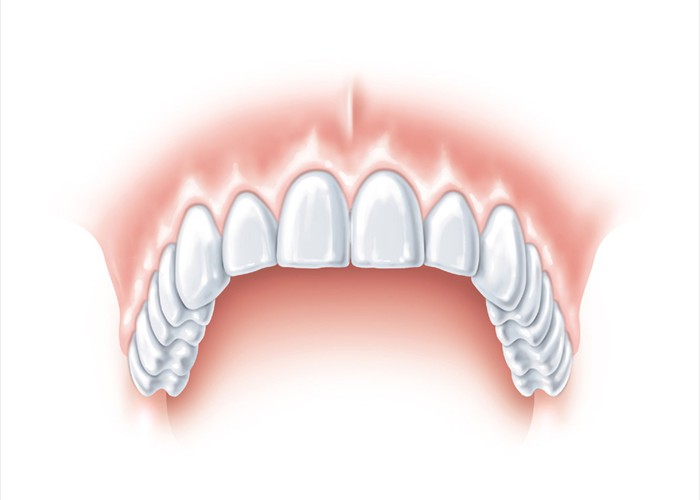

Zahnloser Oberkiefer - bei einer klassischen Versorgung müsste hier eine totale Prothese eingegliedert werden.

Zahnloser Oberkiefer - bei einer klassischen Versorgung müsste hier eine totale Prothese eingegliedert werden.